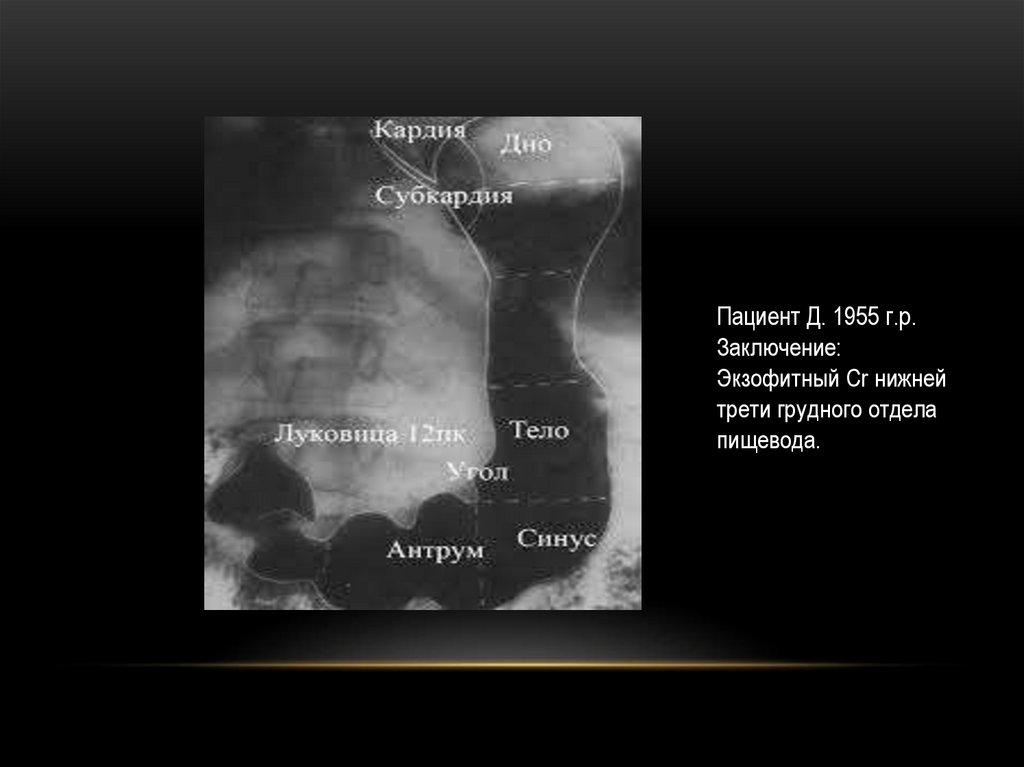

Пациент Д. 1955 г.р.

Заключение:

Экзофитный Cr нижней

трети грудного отдела

пищевода.